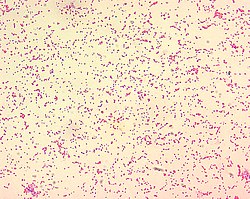

Brucellaceae je porodica bakterija iz reda Rhizobales.